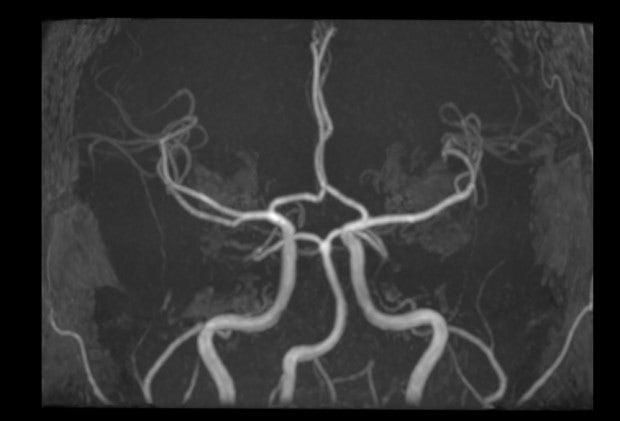

• 2번 째 사진

환자분이 보여주신 circle of willis 와 같은 큰 혈관은 특별한 이상이 보이지 않지만 뇌에는 보여주신 영상에 나타나는 것 이외에도 혈관투성이니까요.